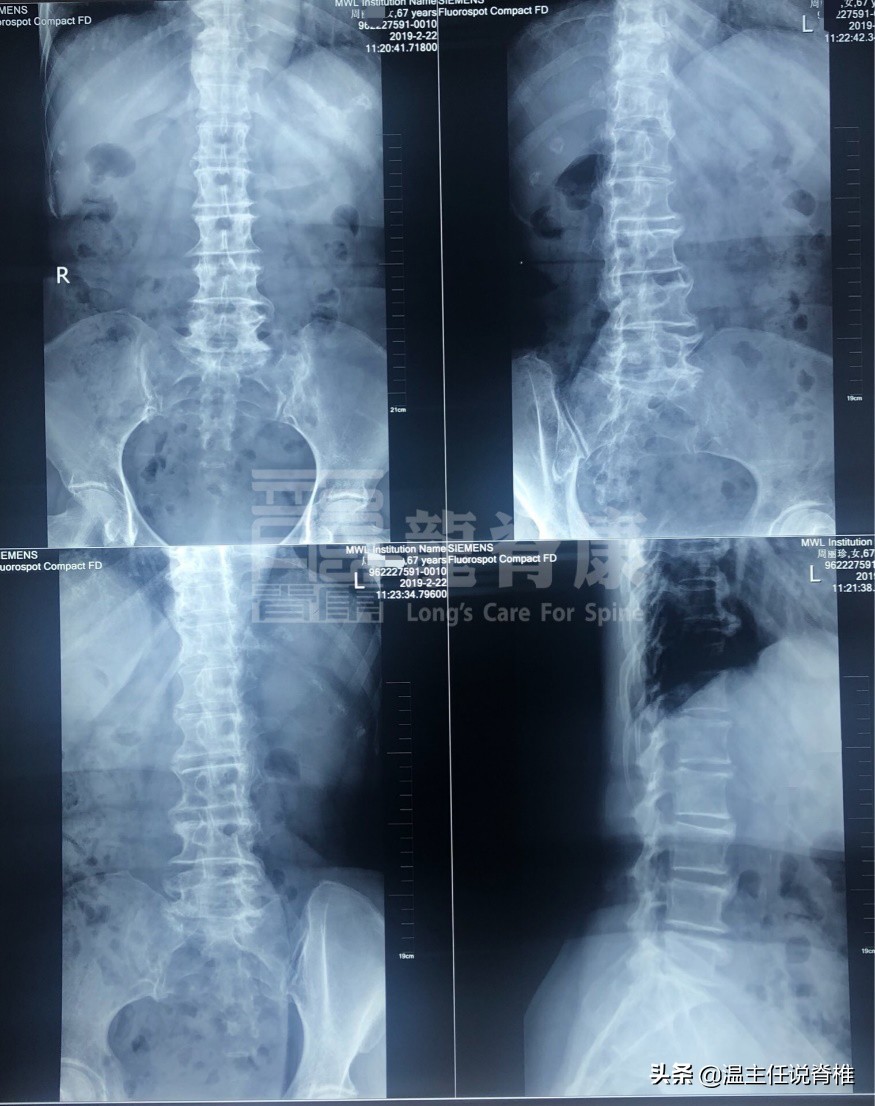

经仔细询问、触诊及X光辅助检查,综合周姨检查报告如下:

腰椎生理曲度变直,部分锥小关节骨质增生

两侧髂骨翼,坐骨结节,髋臼缘,骶髂关节下缘不同程度骨质增生变尖

双膝关节内侧稍狭窄,双侧髌骨后缘增生硬化